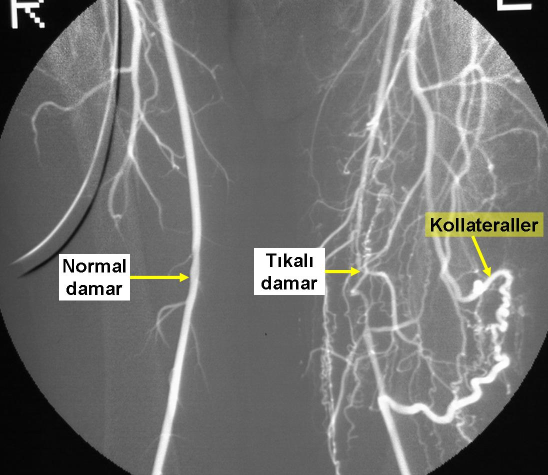

Vücudumuzdaki atardamarların tıkanması bazı durumlarda iskemi yaratmayabilir. Bu durumda ya o dokuyu besleyen başka damarlar bulunabilir ya da vücudumuz o tıkanıklığın iki ucunu birbirine bağlayan yeni damarlar oluşturmuştur. Kollateral adı verilen bu damarlar çok sayıda, küçük çaplı ve kıvrıntılıdır.

Bir hastada, sol femoral damar tıkanıklığı sonucu oluşan kollateraller

Kollateraller genellikle istirahat halindeyken dokunun ihtiyacına yetecek kadar bir kan akımı sağlayabilir, ancak yürüme, koşma gibi dokularımızın kan ihtiyacının arttığı durumlarda yetersiz kalırlar ve dokuda iskemi oluşumuna engel olamazlar.